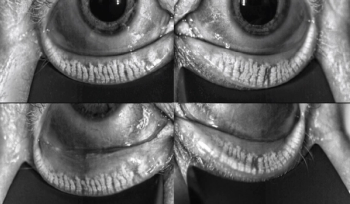

Cynthia Matossian, MD, FACS, ABES, discusses the big disconnect between signs and symptoms of ocular surface disease, including meibomian gland dysfunction, and why a clear process for educating patients and initiating treatment is essential.

Cynthia Matossian, MD, FACS, advises on how ophthalmologists can start performing a better diagnosis of ocular surface disease in three simple steps.

Cynthia Matossian, MD, FACS, explains why she believes if ophthalmologists consistently evaluate the ocular surface, tear film and lid margins—and treat any problems that we find—surgical outcomes will improve.